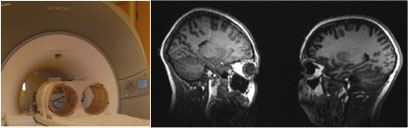

בכנס השנתי של האגודה הבינלאומית למדעי המוח שהתקיים בנובמבר האחרון בסן דייגו, דיווח הפיזיקאי ריי לי מפרינסטון על התפתחות טכנולוגית מרעישה: סורק דו-ראשי. ריי הצליח לפתח שני צילינדרים (head coils) נפרדים ולהציב ביניהם חלון המאפשר לשני אנשים לראות אחד את השני ולגעת זה בזה בזמן שמוחם נסרק.

סורק דו-ראשי (צילום: Ray Lee, 2010, Society for Neuroscience, abstract 303.13)

בניסוי המבחן ביקש לי מבני זוג לפתוח ולסגור את עיניהם בו-זמנית. כצפוי, במוחם של בני הזוג נמצאה קורלציה בפעילות העצבית באזור הסולקוס הטמפורלי (STS)

שמתווך תפיסת פרצופים ומעבד את כיוון המבט (gaze), אינפורמציה הנדרשת לתקשורת חברתית.